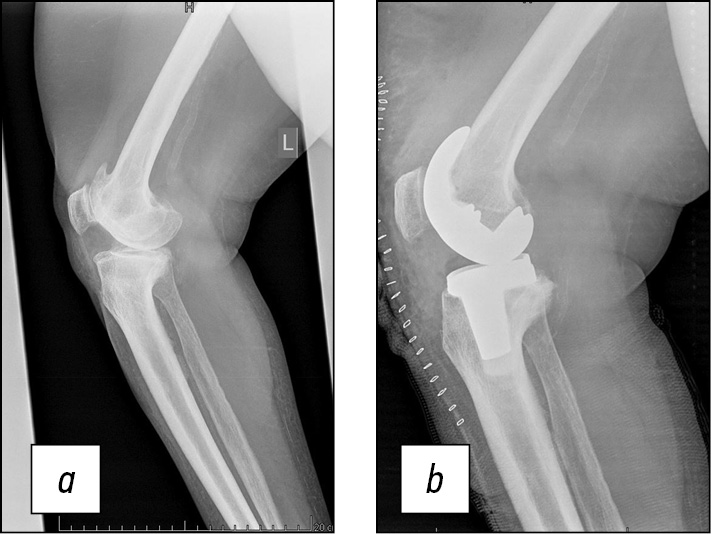

Последующие этапы, подготавливающие уже непосредственно к установке компонентов эндопротеза коленного сустава, выполняются штатно, в том числе с последующей оценкой балансировки сгибательного и разгибательного промежутков, проверкой запланированных ранее размеров на примерочных компонентах эндопротеза. Затем выполняется уже финальная установка компонентов эндопротеза коленного сустава. В данном случае размеры полностью совпали с предоперационным планом (бедренный компонент Zimmer, размер D, плато большеберцовой кости № 3) (рис. 10). Рана послойно ушита, выполнены контрольные рентгеновские снимки в прямой и боковой проекциях (рис. 11, 12).

Рис. 11. Рентгенограммы больной Т. в прямой проекции: а — до оперативного лечения, b — после оперативного лечения.

Fig. 11. Radiographs of patient T. in frontal projection: a — before surgical treatment, b — after surgical treatment.

Рис. 12. Рентгенограммы больной Т. в боковой проекции: а — до оперативного лечения, b — после оперативного лечения.

Fig. 12. Radiographs of patient T. in lateral projection: a — before surgical treatment, b — after surgical treatment.